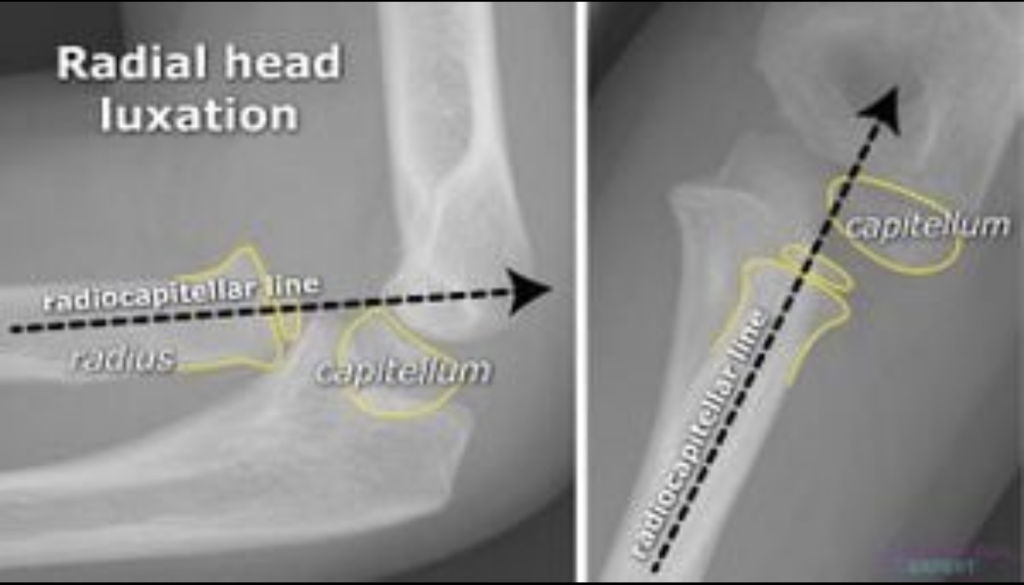

Radiocapitellar line, dirsek grafilerinde (özellikle çocuklarda) radius başı ile kapitellum hizasını değerlendirmek için kullanılan temel bir radyolojik referans çizgisidir.